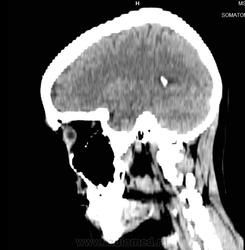

Ушиб головного мозга непонятной степени.

................Ударилась об асфальт  правой стороной головы.

Эти снимки сделаны на сороковой день после травмы. На снимках непонятные мне: белое пятно, темное возле шеи и засветленная макушка и еще какая-то белая полоса. Что это?Доктор сказал, что у меня все хорошо. Хотя чувствую себя не очень.

Данных картинок для диагностики явно мало.Вы считаете, что выбрали самые показательные , на Ваш взгляд, снимки ?Нужны дайкомы.Выкладывайте.Коллеги, занимающиеся КТ, думаю, что помогут.